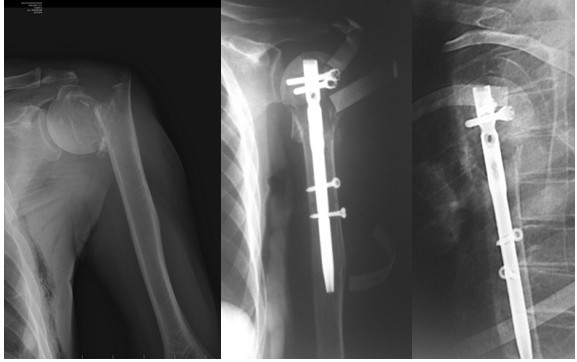

Реконструкция плевой кости штифтом